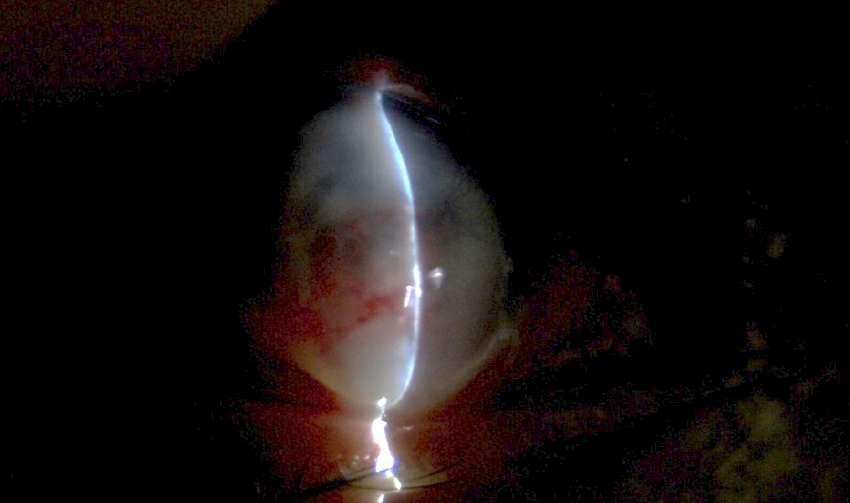

7.B. CATARATA LAMELAR

Imágenes aportadas por Dr. Álvaro Rodriguez

BAü La catarata lamelar también denominada zonular, es la más frecuente de las cataratas infantiles.

ü Se puede heredar en forma autosómica dominante.

ü Se presentan como opacidades bilaterales del núcleo y son el resultado de un daño al cristalino durante el desarrollo fetal siendo las capas más internas afectadas en mayor importancia mientras más precoz haya sido el daño.

ü Clínicamente se caracteriza por la presencia de opacidades en el cristalino que semejan protuberancias en forma de dedos proyectánddose a partir de un núcleo opacificado asociada con regiones de opacidad pulverulenta (Imagen A y B).

Messina O, González L, Cuevas S. Espectro clínico en una familia con catarata lamelar autosómica dominante. Rev Mex Oftalmol; Mayo-Junio 2005; 79(3): 163-165.